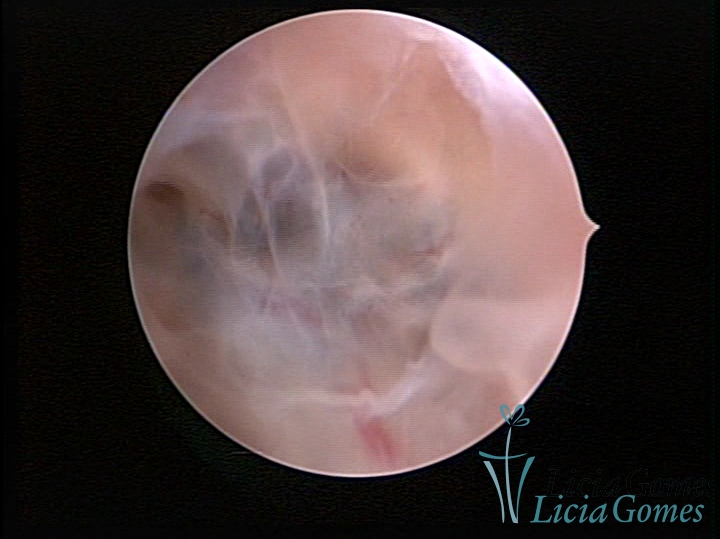

• SINÉQUIA TIPO FIBROMUSCULAR